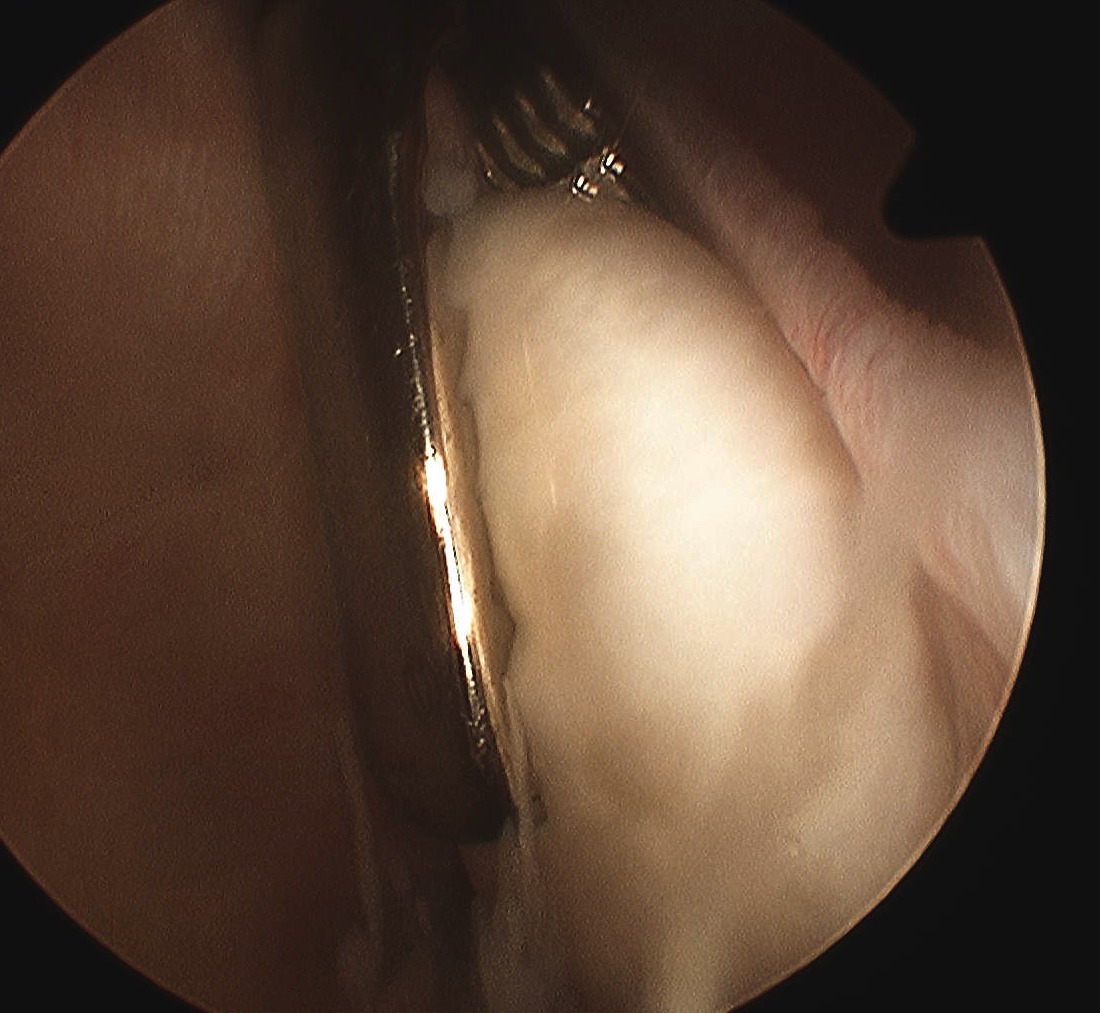

Need to look carefully

Common Sites are

1. Notch

- can be covered by soft tissue

5. Loose body can be adhered and covered in synovium